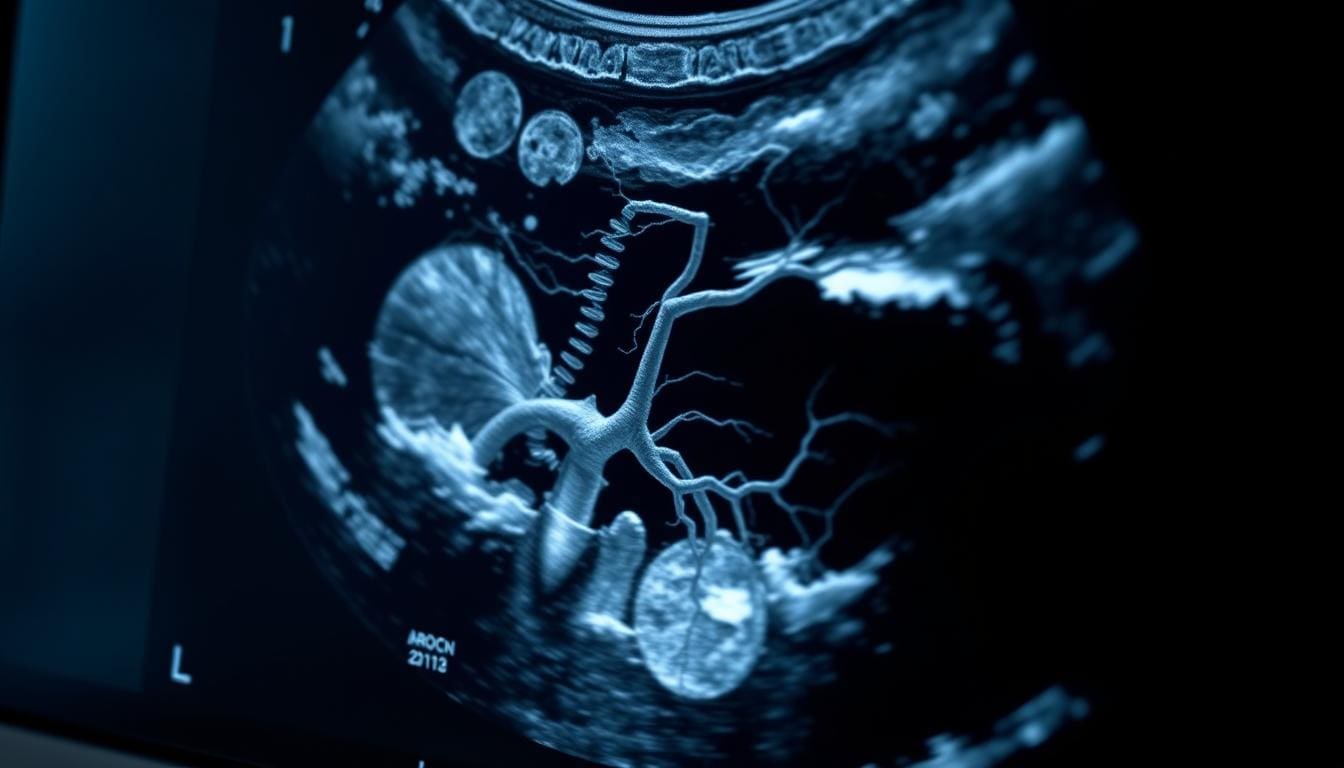

An abdominal aorta sonogram is a non-invasive test that checks the health of the abdominal aorta. It’s key for finding abdominal aortic aneurysms (AAAs). These can be deadly if not caught early.

The Non-Invasive Nature of Aortic Ultrasound

This test is non-invasive, meaning it doesn’t hurt or cut the body. It uses ultrasound technology to see inside. This makes it safe and easy for patients.

An abdominal aorta sonogram is a simple, non-invasive test. It gives important insights into your vascular health. This test is key for spotting and tracking issues with the abdominal aorta.

You’ll lie on your back on the exam table for this ultrasound. A healthcare pro will put special gel on your belly. This gel helps the sound waves move smoothly.

The Ultrasound Gel and Transducer Experience

The gel lets the transducer glide over your skin, getting clear images of your aorta. The transducer sends sound waves that bounce off your insides. These waves create images on the screen.

Normal Appearance of the Abdominal Aorta

A healthy abdominal aorta looks like a tube with a smooth wall and the same width all the way. Key characteristics include:

- A uniform echo pattern

- No evidence of aneurysmal dilation

- Normal blood flow patterns

In a healthy person, the aorta gets narrower as it goes down into the belly.